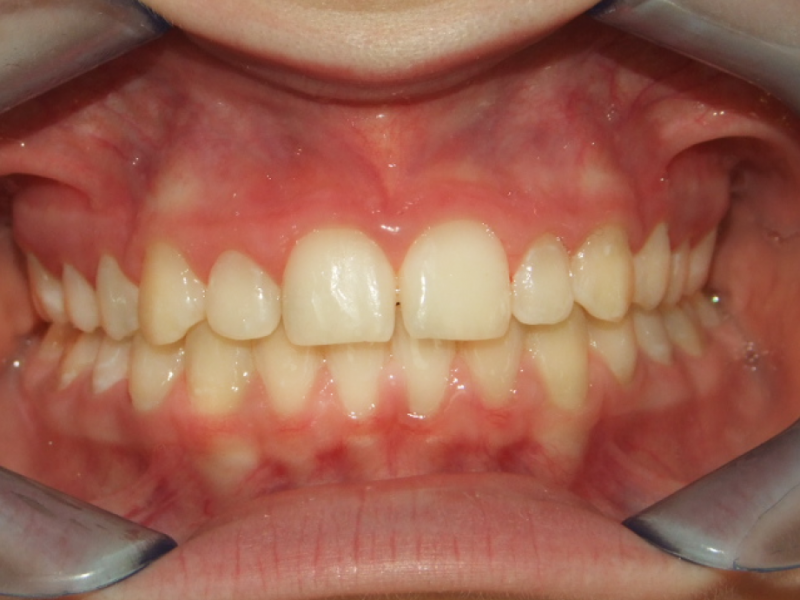

eindfoto

Leeftijd bij aanvang: 9 jaar

Leeftijd bij retentie: 11 jaar